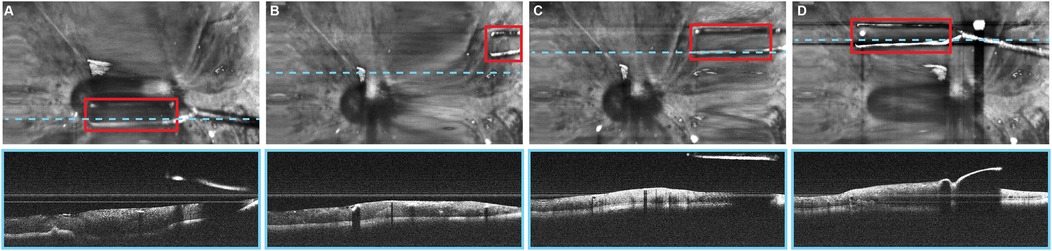

Tang et al. (39) initially developed a deep learning–based adaptively sampled spectrally encoded coherence tomography and reflectometry (SECTR) program for intraoperative optical coherence tomography for real-time imaging during ophthalmic surgical maneuvers. A deep learning model with a CNN was used to track surgical instrument positions and sample instrument tips. The study presented a novel real-time automated tracking of surgical instruments using deep learning.

Tang et al. (3) used a similar method to track surgical instruments, and the results demonstrated a resolution-limited tracking accuracy with a mean pixel error statistically significantly lower than the resolution limit of 2.95 pixels. This finding was also true for speed, depth, and orientation variations. This technology combines multimodal imaging with deep learning and shows high accuracy and speed. It shows promise for improving surgical outcomes by enhancing surgical visualization. Furthermore, tracking surgical instruments can help achieve greater precision during procedures, reduce errors, and make surgical interventions more effective.

Automated instrument tracking using SECTR has also been proposed. This method was used in 2 studies by Tang et al. (39, 47), in which the movements of the 25G ILM forceps, a surgical instrument, were tracked by spectrally encoded reflectometry. The forceps were tracked by training a CNN, allowing 4-dimensional (4D) visualization of surgical motion during ophthalmological surgeries (Figure 6) (39, 47).

Figure 6. Automated instrument-tracking using SECTR. Tang et al. (39) trained a CNN to track 25G ILM forceps, a surgical instrument, to allow 4D visualization of the surgical motion during ophthalmologic surgeries. (A) Five-averaged SER image and representative OCT image demonstrating the tip of the forceps (red box) in an ex vivo bovine eye. Movement of the instrument out of the OCT plane (blue dashed line) and adaptive sampling can be seen on (B–D). CNN, convolutional neural network; OCT, optic coherence tomography; SECTR, spectrally encoded coherence tomography and reflectometry; SER, spectrally encoded reflectometry; 4D, four-dimensional. Used with permission from Tang E, El-Haddad M, Malone JD, et al. Automated instrument-tracking using deep-learning-based adaptively-sampled spectrally encoded coherence tomography and reflectometry (SECTR). Investigative Ophthalmology & Visual Science. 2019;60(9):1276-1276.

4.3.8 Instrument tracking and adaptive sampling models for 4D imaging

Tang et al. proposed a deep learning–based automated instrument tracking and adaptive sampling model that could be used for 4D imaging of ophthalmic surgical maneuvers (3). The findings indicate that real-time localization of surgical instruments can be achieved using SECTR with the deep learning model. Moreover, adaptive sampling enhances the visualization of instrument-tissue interactions by increasing sampling density without sacrificing speed (3).